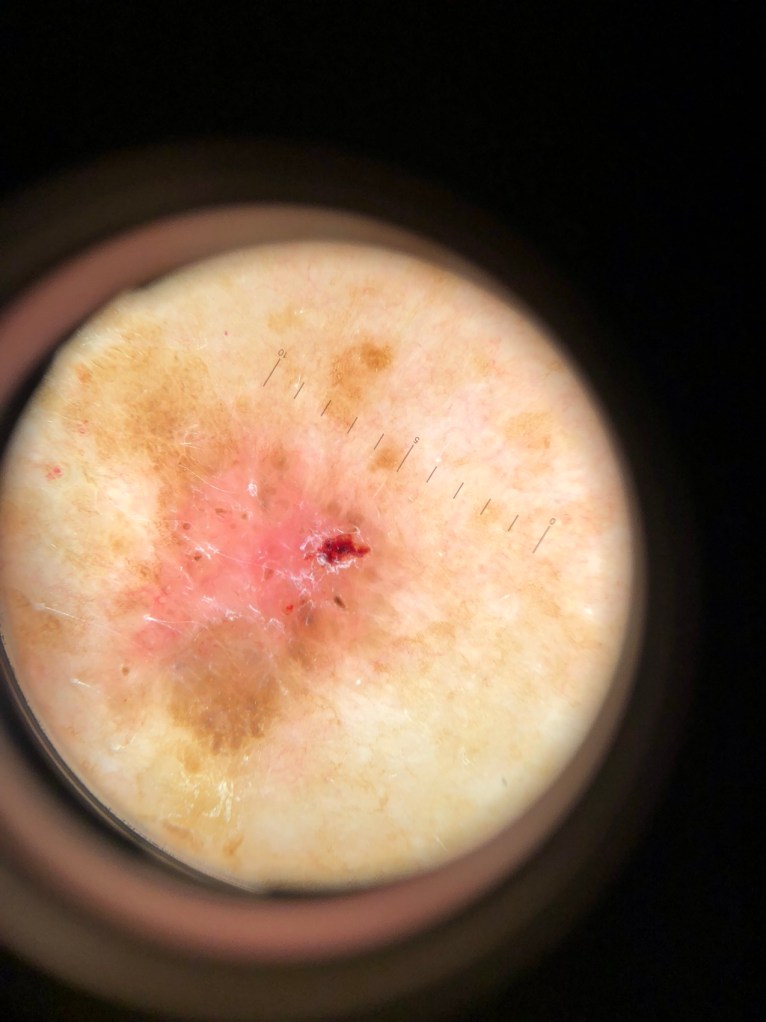

Seuraavana muutamia luomikuvia ja heti perään valokuva joka otettu dermatoskoopin kautta. Testaa itsesi jos tunnistat ko. muutokset!

Potilas 4, rintakehä:

Potilas 5, yläselässä kaksi punoittavaa muutosta jotka eroavat rasvasyylistä:

Eli kuvissa näkyy selkeästi ihomuutosten tarkempi rakenne dermatoskooppikuvissa.

Potilas 4: rintakehällä pinnallisesti leviävä melanooma.

Potilas 5: yläselässä kaksi erillistä basalioomaa eli tyvisolusyöpää.